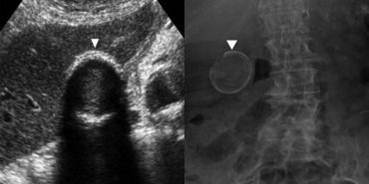

Cholelithiasis

(These small stones are “floating” on sludge

This is layering)